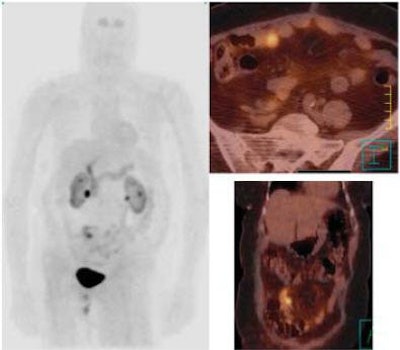

![]() |

| Same case as above. 111In-pentetreotide SRS provided a doubtful result with negative images 4 hours after injection of 111In-pentetreotide (left) and a doubtful abdominal focus 24 hours after injection (right). Primary small bowel carcinoid was subsequently successfully resected. Copyright © 2006 by the Society of Nuclear Medicine. |